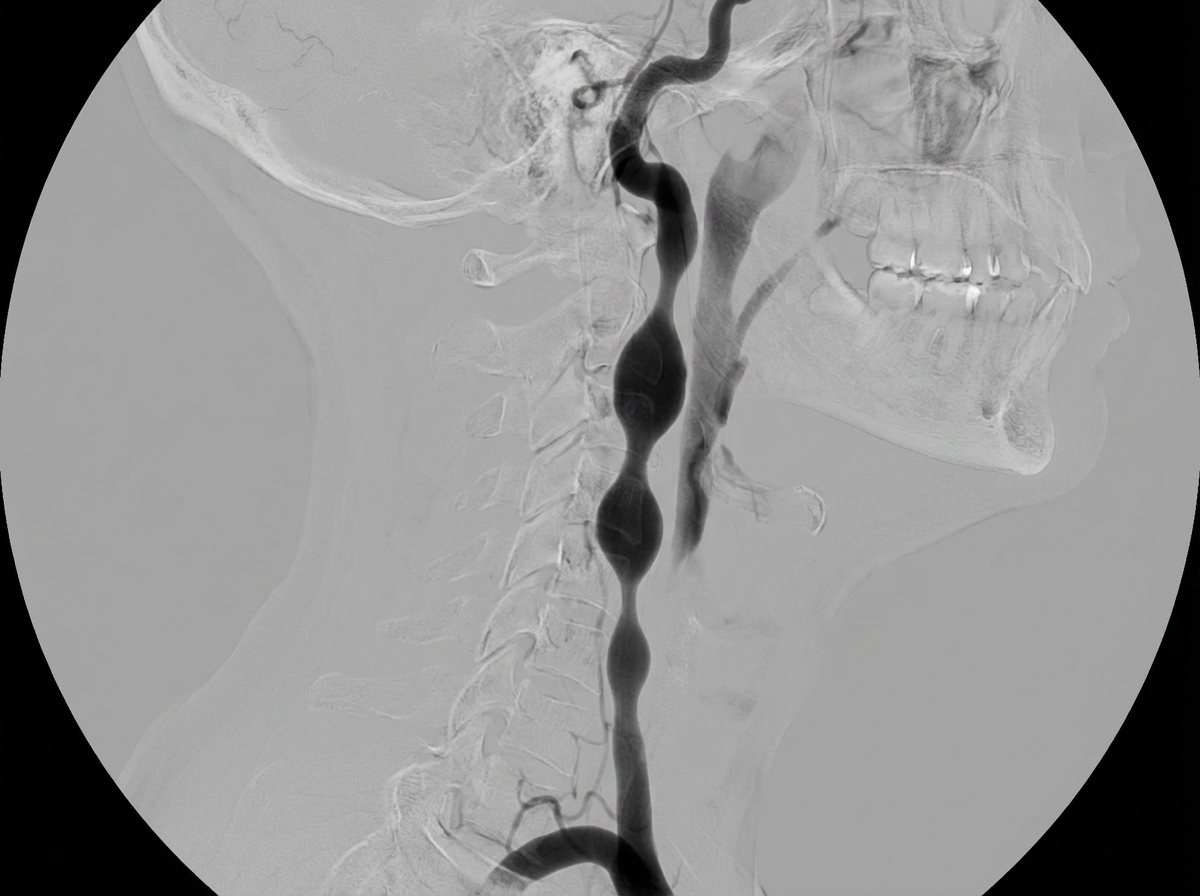

A 35-year-old female presented with a history of multiple transient ischemic attacks. What is the most likely diagnosis suggested by the given carotid angiogram?

Explanation: ***Fibromuscular dysplasia*** - Classic **"string of beads"** appearance on angiography in a **young female** with TIAs is pathognomonic for fibromuscular dysplasia. - This **non-atherosclerotic** vascular disease commonly affects the **renal** and **carotid arteries** in women aged 20-60 years. *Atherosclerosis* - Typically presents as **smooth, eccentric plaques** rather than the characteristic beaded appearance. - More common in **older patients** with traditional cardiovascular risk factors like smoking, diabetes, and hypertension. *Thrombosis* - Would appear as an **abrupt cutoff** or **filling defect** within the vessel lumen on angiography. - Usually associated with **acute onset** symptoms rather than recurrent transient episodes. *Carotid dissection* - Angiographic findings include **tapering stenosis** with a characteristic **flame-shaped** narrowing or **double lumen** sign. - Often presents with **sudden severe headache** or neck pain along with neurological symptoms.